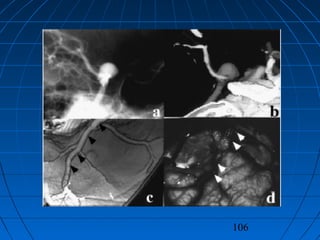

İİNTRAKRANYALNTRAKRANYAL AANEVRİZMALARINNEVRİZMALARIN PPATOGENEZİATOGENEZİ

Anevrizma Görüntülenmesinde YeniAnevrizma Görüntülenmesinde Yeni

TekniklerTeknikler